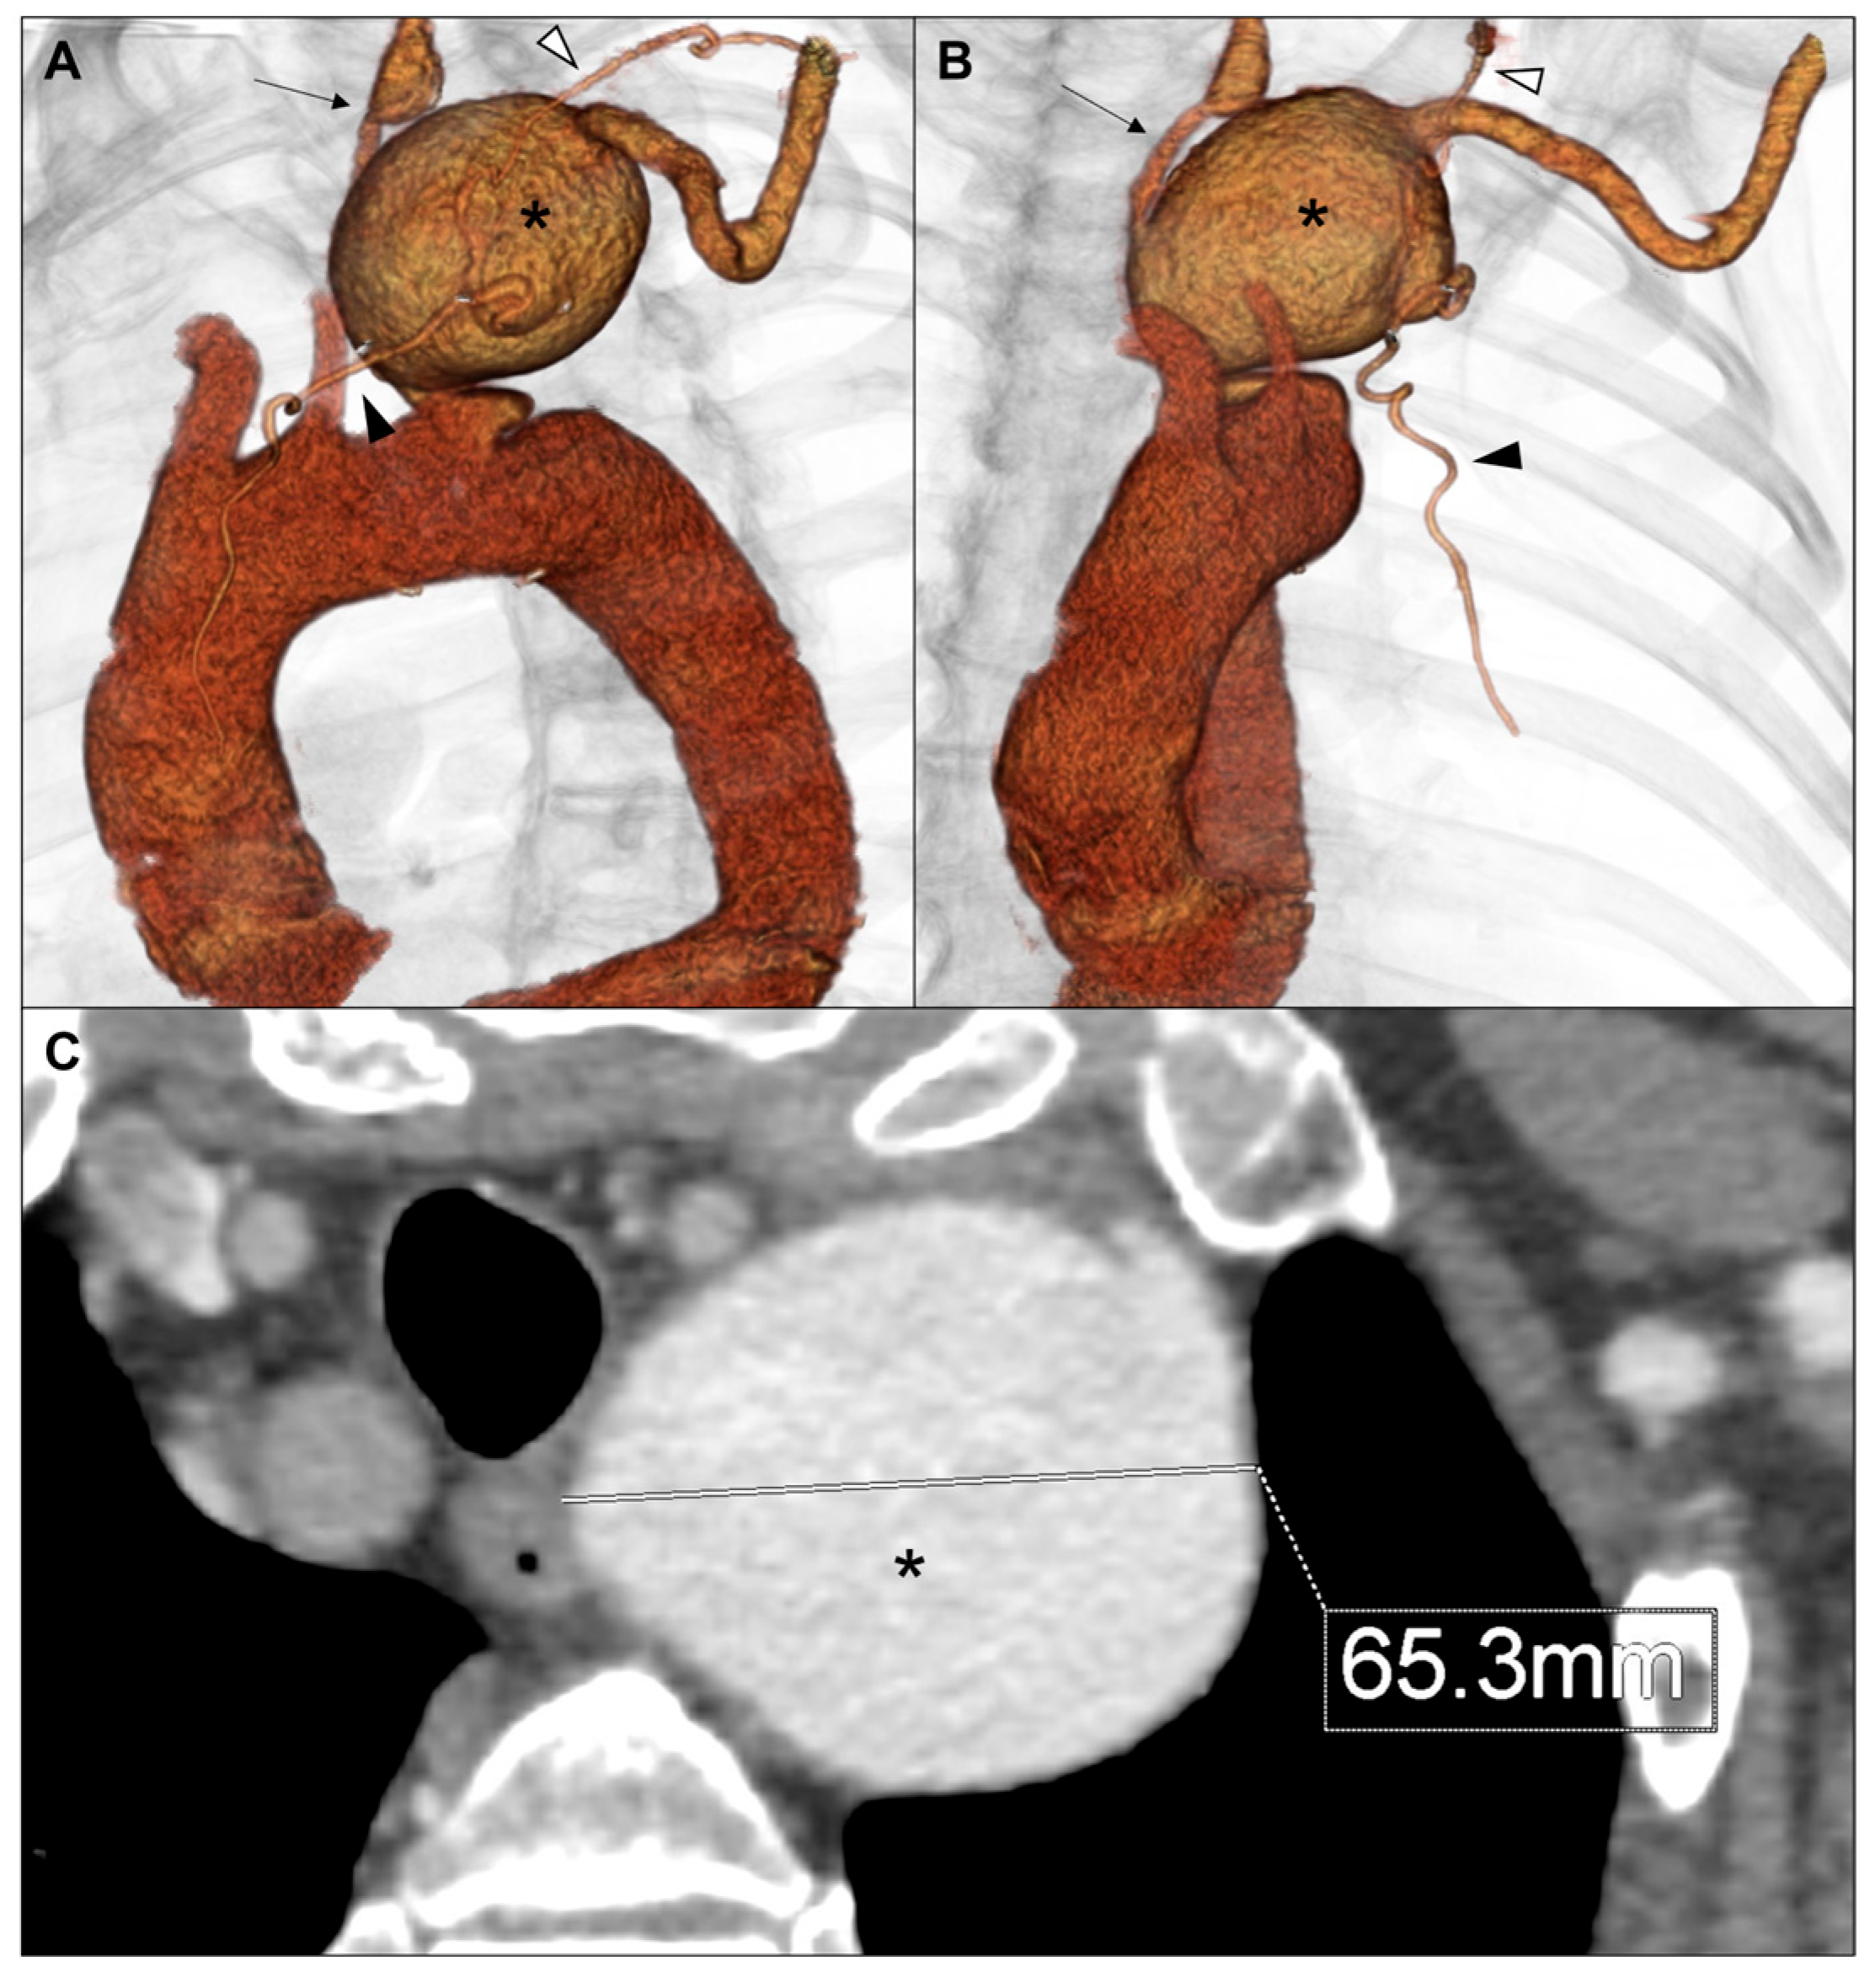

2. Case Report